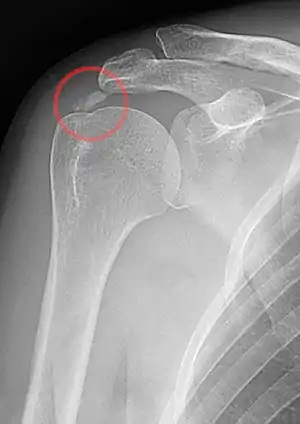

| A plain X ray of the shoulder showing calcific tendinitis | |

Calcific tendinitis is typically diagnosed by physical examination and X-ray imaging.[1] During the formative phase, X-ray images typically reveal calcium deposits with uniform density and a clear margin.[1] In the more painful resorptive phase, deposits instead appear cloudy and with unclear margins.[1] By arthroscopy, formative stage deposits appear crystalline and chalk-like, while resorptive stage deposits appear smooth resembling toothpaste.[1] Ultrasound is also used to locate and assess calcium deposits. In the formative stage, deposits are hyperechoic and arc-shaped; in the resorptive stage deposits are less echogenic and appear fragmented.[1][3]

An x-ray showing calcific deposits in the area of the tendons of the rotator cuff muscles